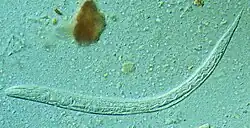

First stage larva (L1) of S. stercoralis

Strongyloides (from Greek strongylos, round, + eidos, resemblance), anguillula, or threadworm is a genus of small nematode parasites, belonging to the family Strongylidae, commonly found in the small intestine of mammals (particularly ruminants), that are characterized by an unusual lifecycle that involves one or several generations of free-living adult worms.